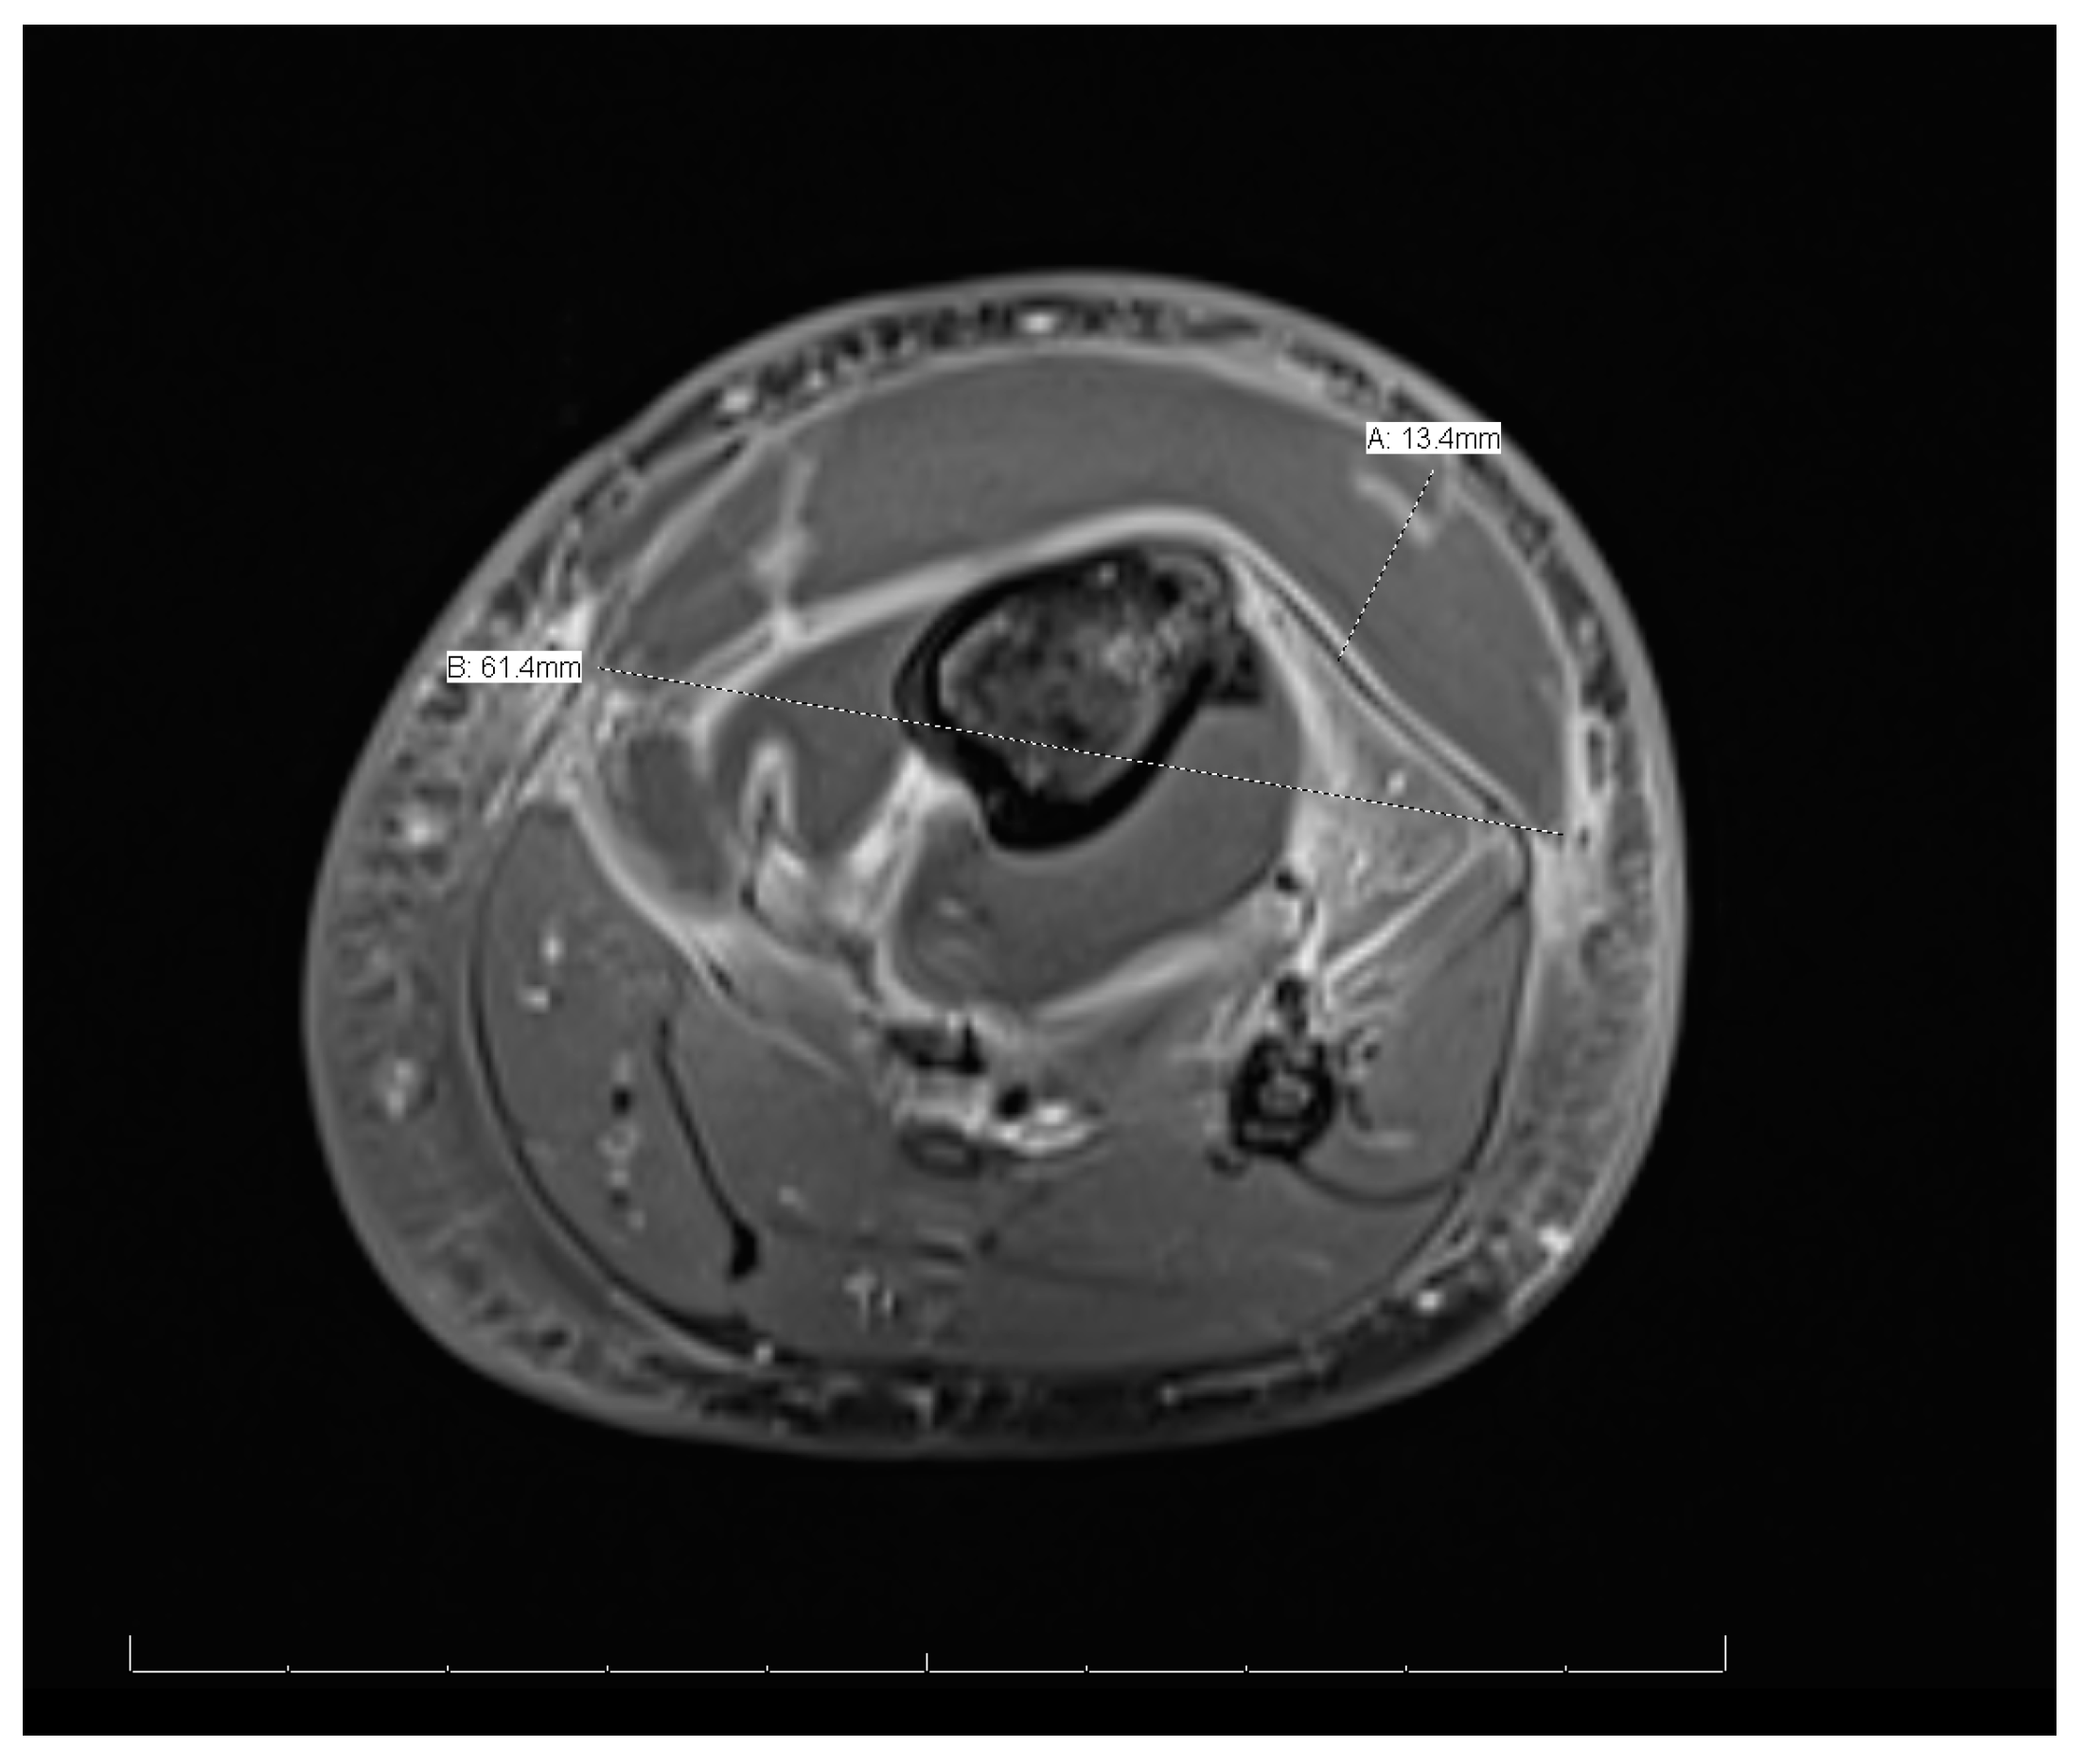

MRI of the left leg (Figure 3 and Figure 4): The whole left tibial bone shaft (proximal, mid, and distal), including the proximal epiphysis, showed a diffuse, multiple, heterogeneous marrow signal, intermediate to low on T1 and high on T2, as well as bone marrow edema associated with a periosteal reaction seen mainly on the medial aspect of the proximal metaphysis of the tibia. This is a large lobulated/septated periosteal collection surrounding all aspects of the proximal region and the mid-shaft of the left tibia bone. The collection ran along posteriorly for a distance of 13.3 cm × 3.2 cm × 1.4 cm (cranio-caudal [CC], medial–lateral [ML], and anterior–posterior [AP], respectively), with a small pocket extending to the posterior muscle compartment involving the knee joint, which showed joint effusion and synovitis. The anterior part of the collection extended partially to the anterior subcutaneous area and measured 13 × 5.7 × 1.6 (CC, ML, and AP, respectively). Both the anterior and posterior parts of the collections were connected. A focal cortical defect was evident at the anterior medial aspect of the proximal tibial epiphysis (T2 STIR axial 15/44 image), with an adjacent periosteal collection. The fibula, femur, and ankle joint were not involved and showed a normal signal. Diffuse soft tissue swelling was evident, mainly in the proximal part of the leg. The muscles around the leg and knee joint appeared to be normal. The MRI findings were in line with acute osteomyelitis of the left tibia, with periosteal collections.

Figure 3.

Magnetic resonance imaging of the whole left leg.

Figure 4.

Magnetic resonance imaging of the whole left leg (cross-sectional view).